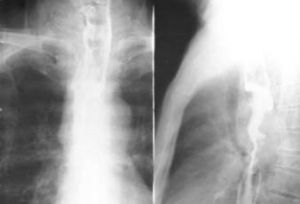

對可疑病例,均應做食管吞稀鋇X線雙重對比造影。早期可見:①食管黏膜皺襞紊亂、粗糙或有中斷現象;②小的充盈缺損;③局限性管壁僵硬,蠕動中斷;④小龕影。中、晚期有明顯的不規則狹窄和充盈缺損,管壁僵硬。有時狹窄上方口腔側食管有不同程度的擴張。B超檢查是否有肝臟等臟器轉移。實驗室檢查貧血程度和癌胚抗原檢測。CT檢查有無腦部、肺部等處轉移。

早期無咽下困難時,應與食管炎、食管憩室和食管靜脈曲張相鑑別。已有咽下困難時,應與食管良性腫瘤、賁門失弛症和食管良性狹窄相鑑別。鑑別診斷方法主要依靠吞鋇X線食管攝片和纖維食管鏡檢查。